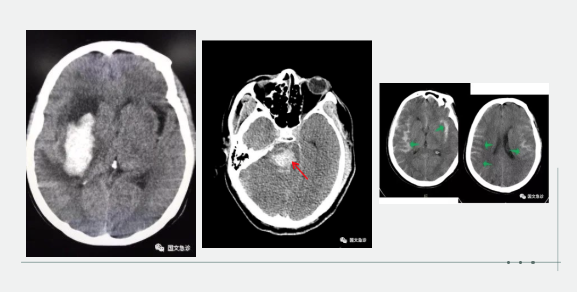

突發(fā)意識不清兩小時(shí)入院。據(jù)家屬描述“發(fā)現(xiàn)的時(shí)候老爺子躺在地上叫了好幾聲也沒有反應(yīng),上去推了推也沒動靜趕忙就打120了。根據(jù)該家屬的描述,緊急為患者進(jìn)行查體:該患者意識成昏迷狀態(tài),查體不合作,雙側(cè)瞳孔等大等圓,呼吸間斷 血壓237/115mmhg。內(nèi)科醫(yī)生進(jìn)一步向家屬了解患者既往血壓情況,該家屬表示:“血壓一直都很高,降壓藥也不按時(shí)吃就難受的時(shí)候吃一片”。進(jìn)一步考慮患者腦內(nèi)出血,立即行頭部CT。為患者打開急診綠色通道“遵循檢查或繳費(fèi)的原則”。CT結(jié)果顯示患者左側(cè)大腦半球出血、小腦出血、腦室積血。醫(yī)生立即向家屬交代病情,該家屬哽咽著說:“你說這早上剛還一起吃團(tuán)圓飯呢,一轉(zhuǎn)身的工夫,老爺子就倒地不起了。醫(yī)生您說啊,好好的一個(gè)人怎么就腦出血了?以前除了血壓高一點(diǎn)癥狀都沒有呀!”

突發(fā)意識不清,1小時(shí)入院。該妻子滿眼淚水地向醫(yī)生訴說:“我們剛吃完飯,他說困了睡一會兒,這怎么突然就叫不醒了呢?醫(yī)生您快看看,這是咋了呀?”“李先生平時(shí)身體怎么樣?”“我家老李平時(shí)身體可好了,你別看他長得胖,一年感冒的次數(shù)都少。對了,就是血壓有點(diǎn)高?!备鶕?jù)家屬描述,立即為患者查體:該患者呈深度昏迷狀態(tài),雙側(cè)瞳孔不等大 左側(cè)3.5mm、右側(cè)5.0mm,血壓250/190,雙側(cè)病理征陽性。初步考慮患者腦內(nèi)出血,急行頭部CT檢查。結(jié)果示:右側(cè)小腦及腦干不規(guī)則高密度灶破入腦室,三腦室及四腦室內(nèi)見高密度灶?;颊卟∏槲V蒯t(yī)生立即為患者辦理入院,急忙送往ICU(重癥監(jiān)護(hù)室)進(jìn)行進(jìn)一步治療。